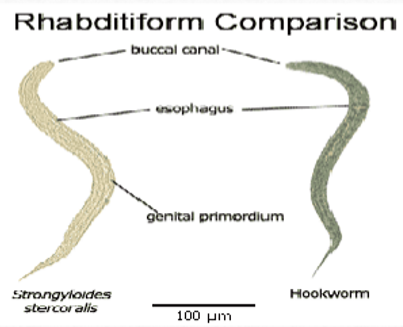

rhabditiform vs filariform

strongyloides stercoralis rhabditiform larvae

Short and sexy

first-stage larva as passed in the feces

esophagus is short (much less than 40% of the body) and distinctly bulbed, the short mouth capsule, and the large genital rudiment (GR)

the latter 2 characteristics distinguish these larvae from those of the hookworms

simple pointed tail

hookworm rhabditiform larvae

Long buccal cavity

More than the width of the body

Genital primordium NOT visible

Esophagus is bulbed

strongyloides rhab vs filariform

rhabditiform: short buccal cavity; esophageal bulb; pointed tail; large genital primoridum

hookworm rhab vs filariform

rhabditiform: long buccal cavity; esophageal bulb; straight tail; small genital primordium

strongyloides rhab vs hookworm rhab

strongyloides: short buccal cavity; esophageal bulb; pointed tail

hookworm: long buccal cavity; esophageal bulb; straight tail